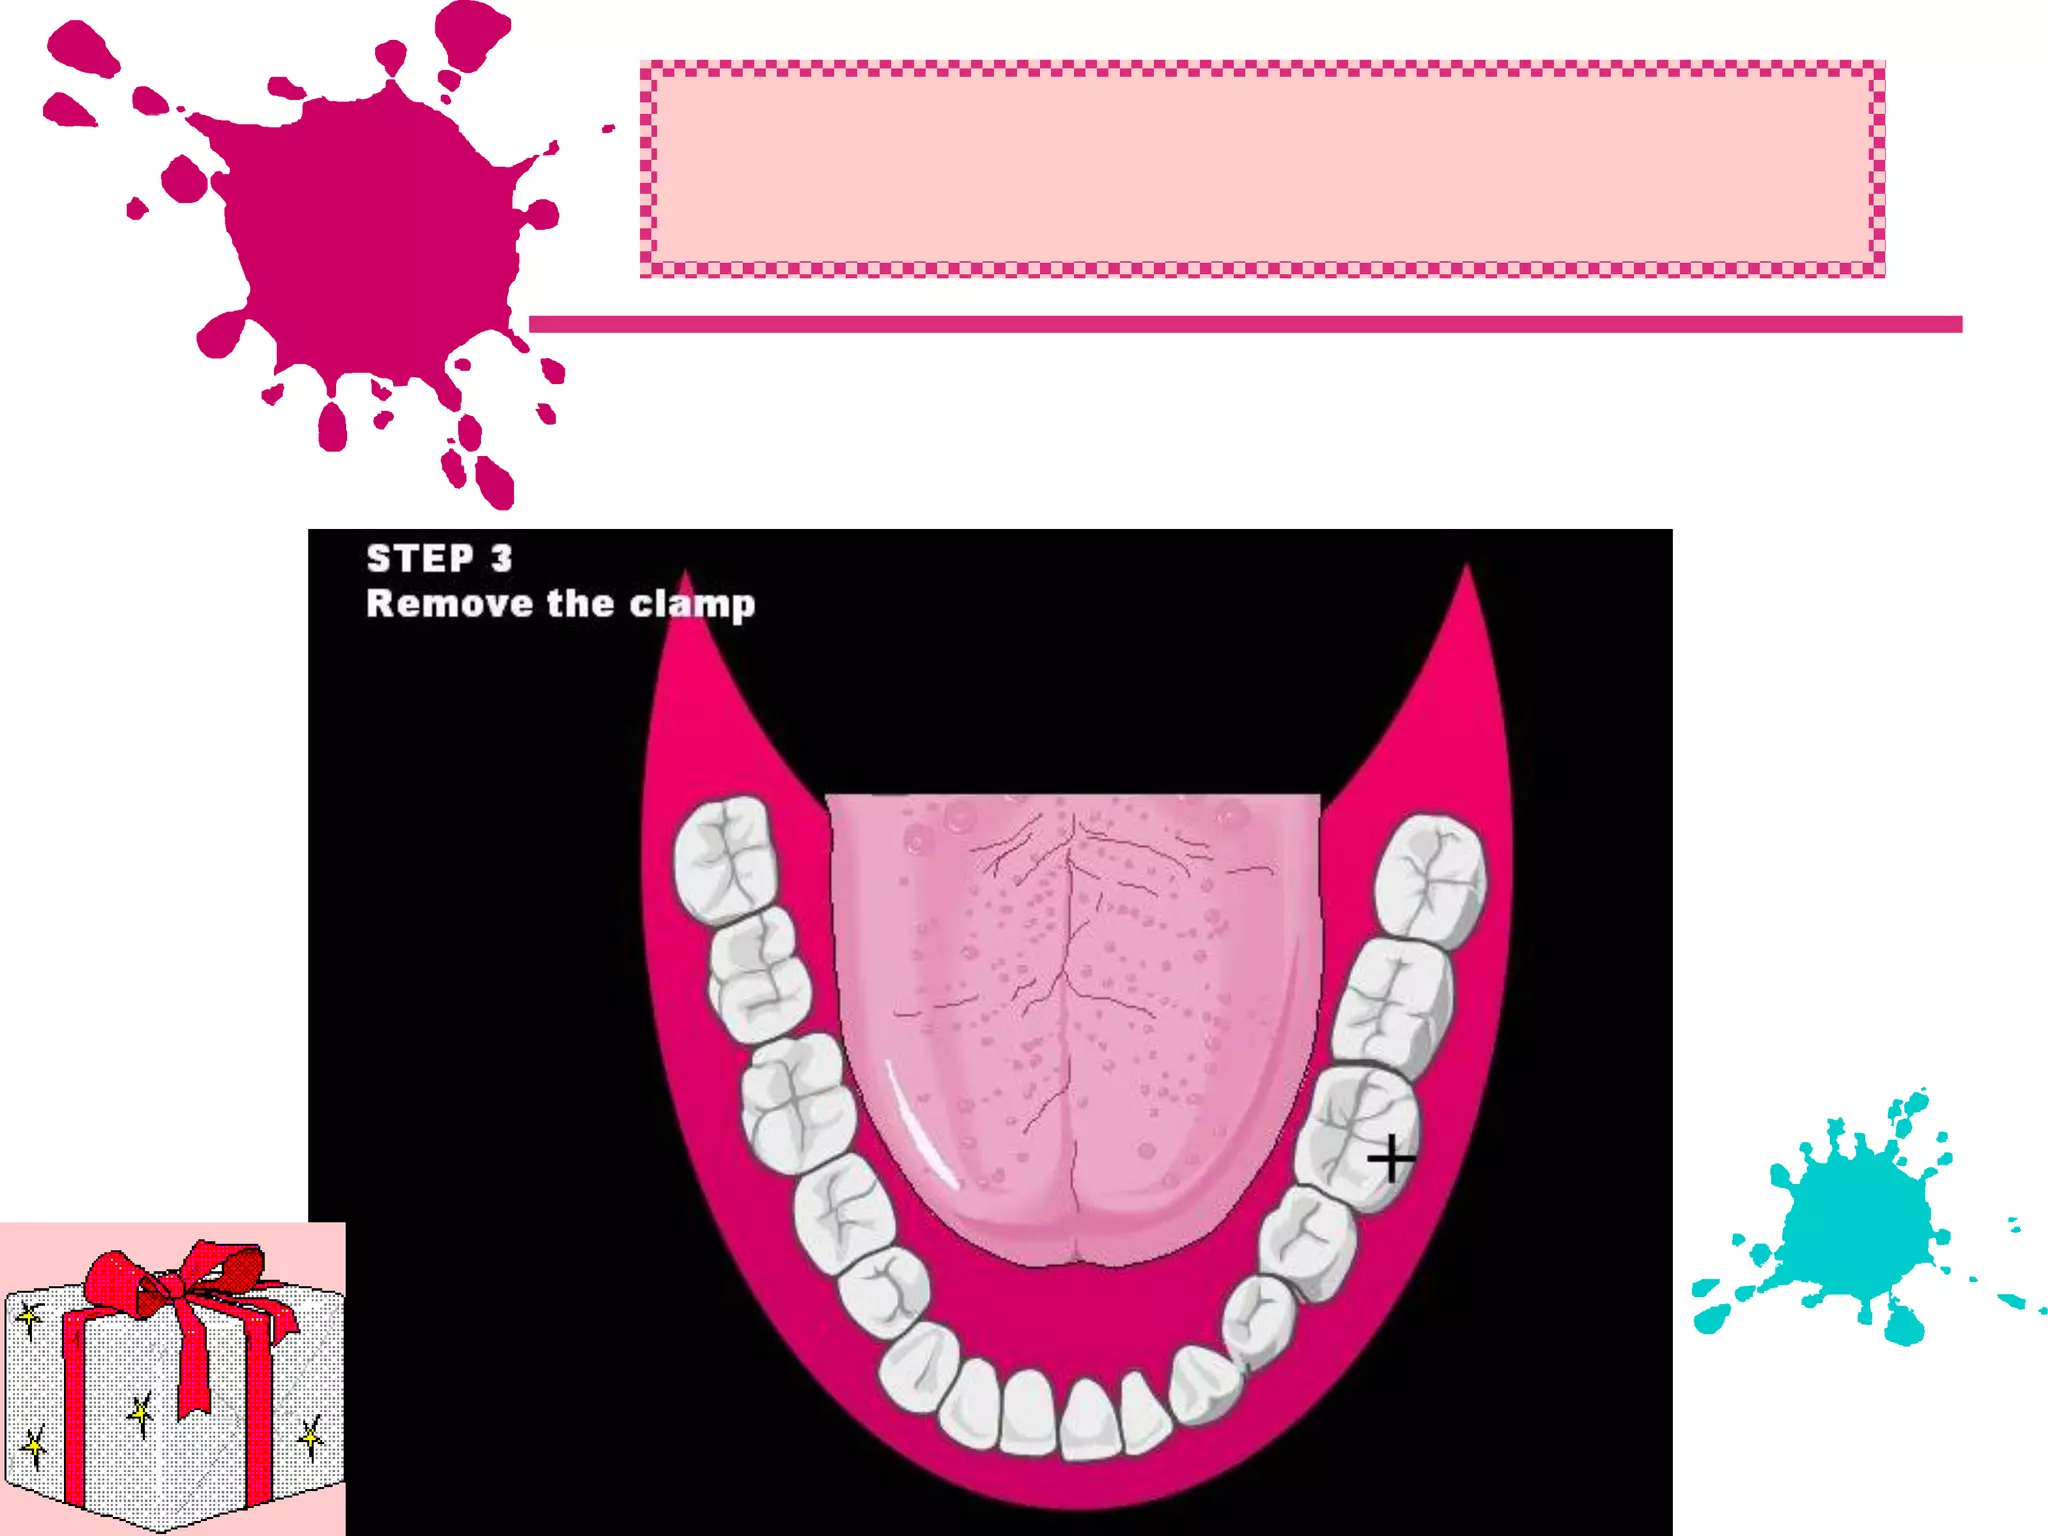

This document discusses the materials and components used for rubber dam isolation in dentistry. It describes the different types of rubber dam materials including color options and napkins to absorb moisture. It also outlines the tools needed such as punches to make holes, templates and stamps to guide hole placement, clamps to secure the dam, and other accessories like wedges and lubricant. Finally, it provides guidance on punching holes for different types of teeth and properly placing clamps in the rubber dam.